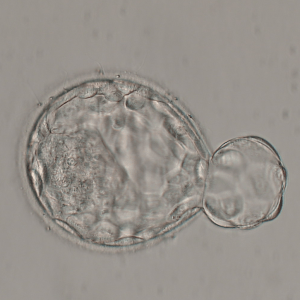

La congélation des embryons est effectuée par une technique appelée vitrification, qui préserve leur qualité et leur potentiel de développement en évitant la cristallisation intracellulaire. Les embryons sont conservés à -196°C, ce qui permet de les préserver sans altérer leur qualité.

Le jour du transfert embryonnaire, nos biologistes et techniciens sélectionnent et décongèlent l’embryon ayant le plus de chances de s’implanter.